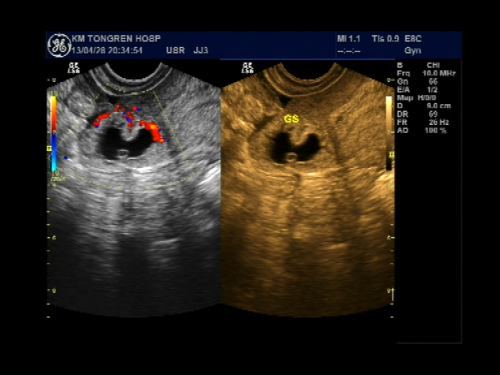

受精卵在子宫体腔以外的地方着床成为异位妊娠,习称宫外孕,是妇产科常见的急腹症,发病率约1%,是孕产妇的主要死亡原因之一。根据受精卵在子宫体外种植部位不同可分为:输卵管妊娠、卵巢妊娠、腹腔妊娠、阔韧带妊娠、宫颈妊娠,其中以输卵管妊娠最常见,占95%左右,而壶腹部妊娠占75%。一般来讲,输卵管有异常的育龄妇女如输卵管炎症、输卵管手术史、输卵管发育不良或功能异常者易导致异位妊娠,其他例如辅助生殖技术、避孕失败、子宫肌瘤或者子宫内膜异位症也容易导致疑问妊娠的发生。根据输卵管妊娠的病理特点可分为以下4型:流产型、破裂型、陈旧性、继发性,主要临床表现是停经后腹痛与阴道出血,当腹腔内出血量大或者疼痛剧烈时可出现晕厥与休克,超声检查下可观察到:宫腔内空虚,宫旁出现似孕囊样包块或者不均质包块,盆腔积液等等,再结合病史、血HCG、尿HCG结果分析,一般可诊断早期异位妊娠。